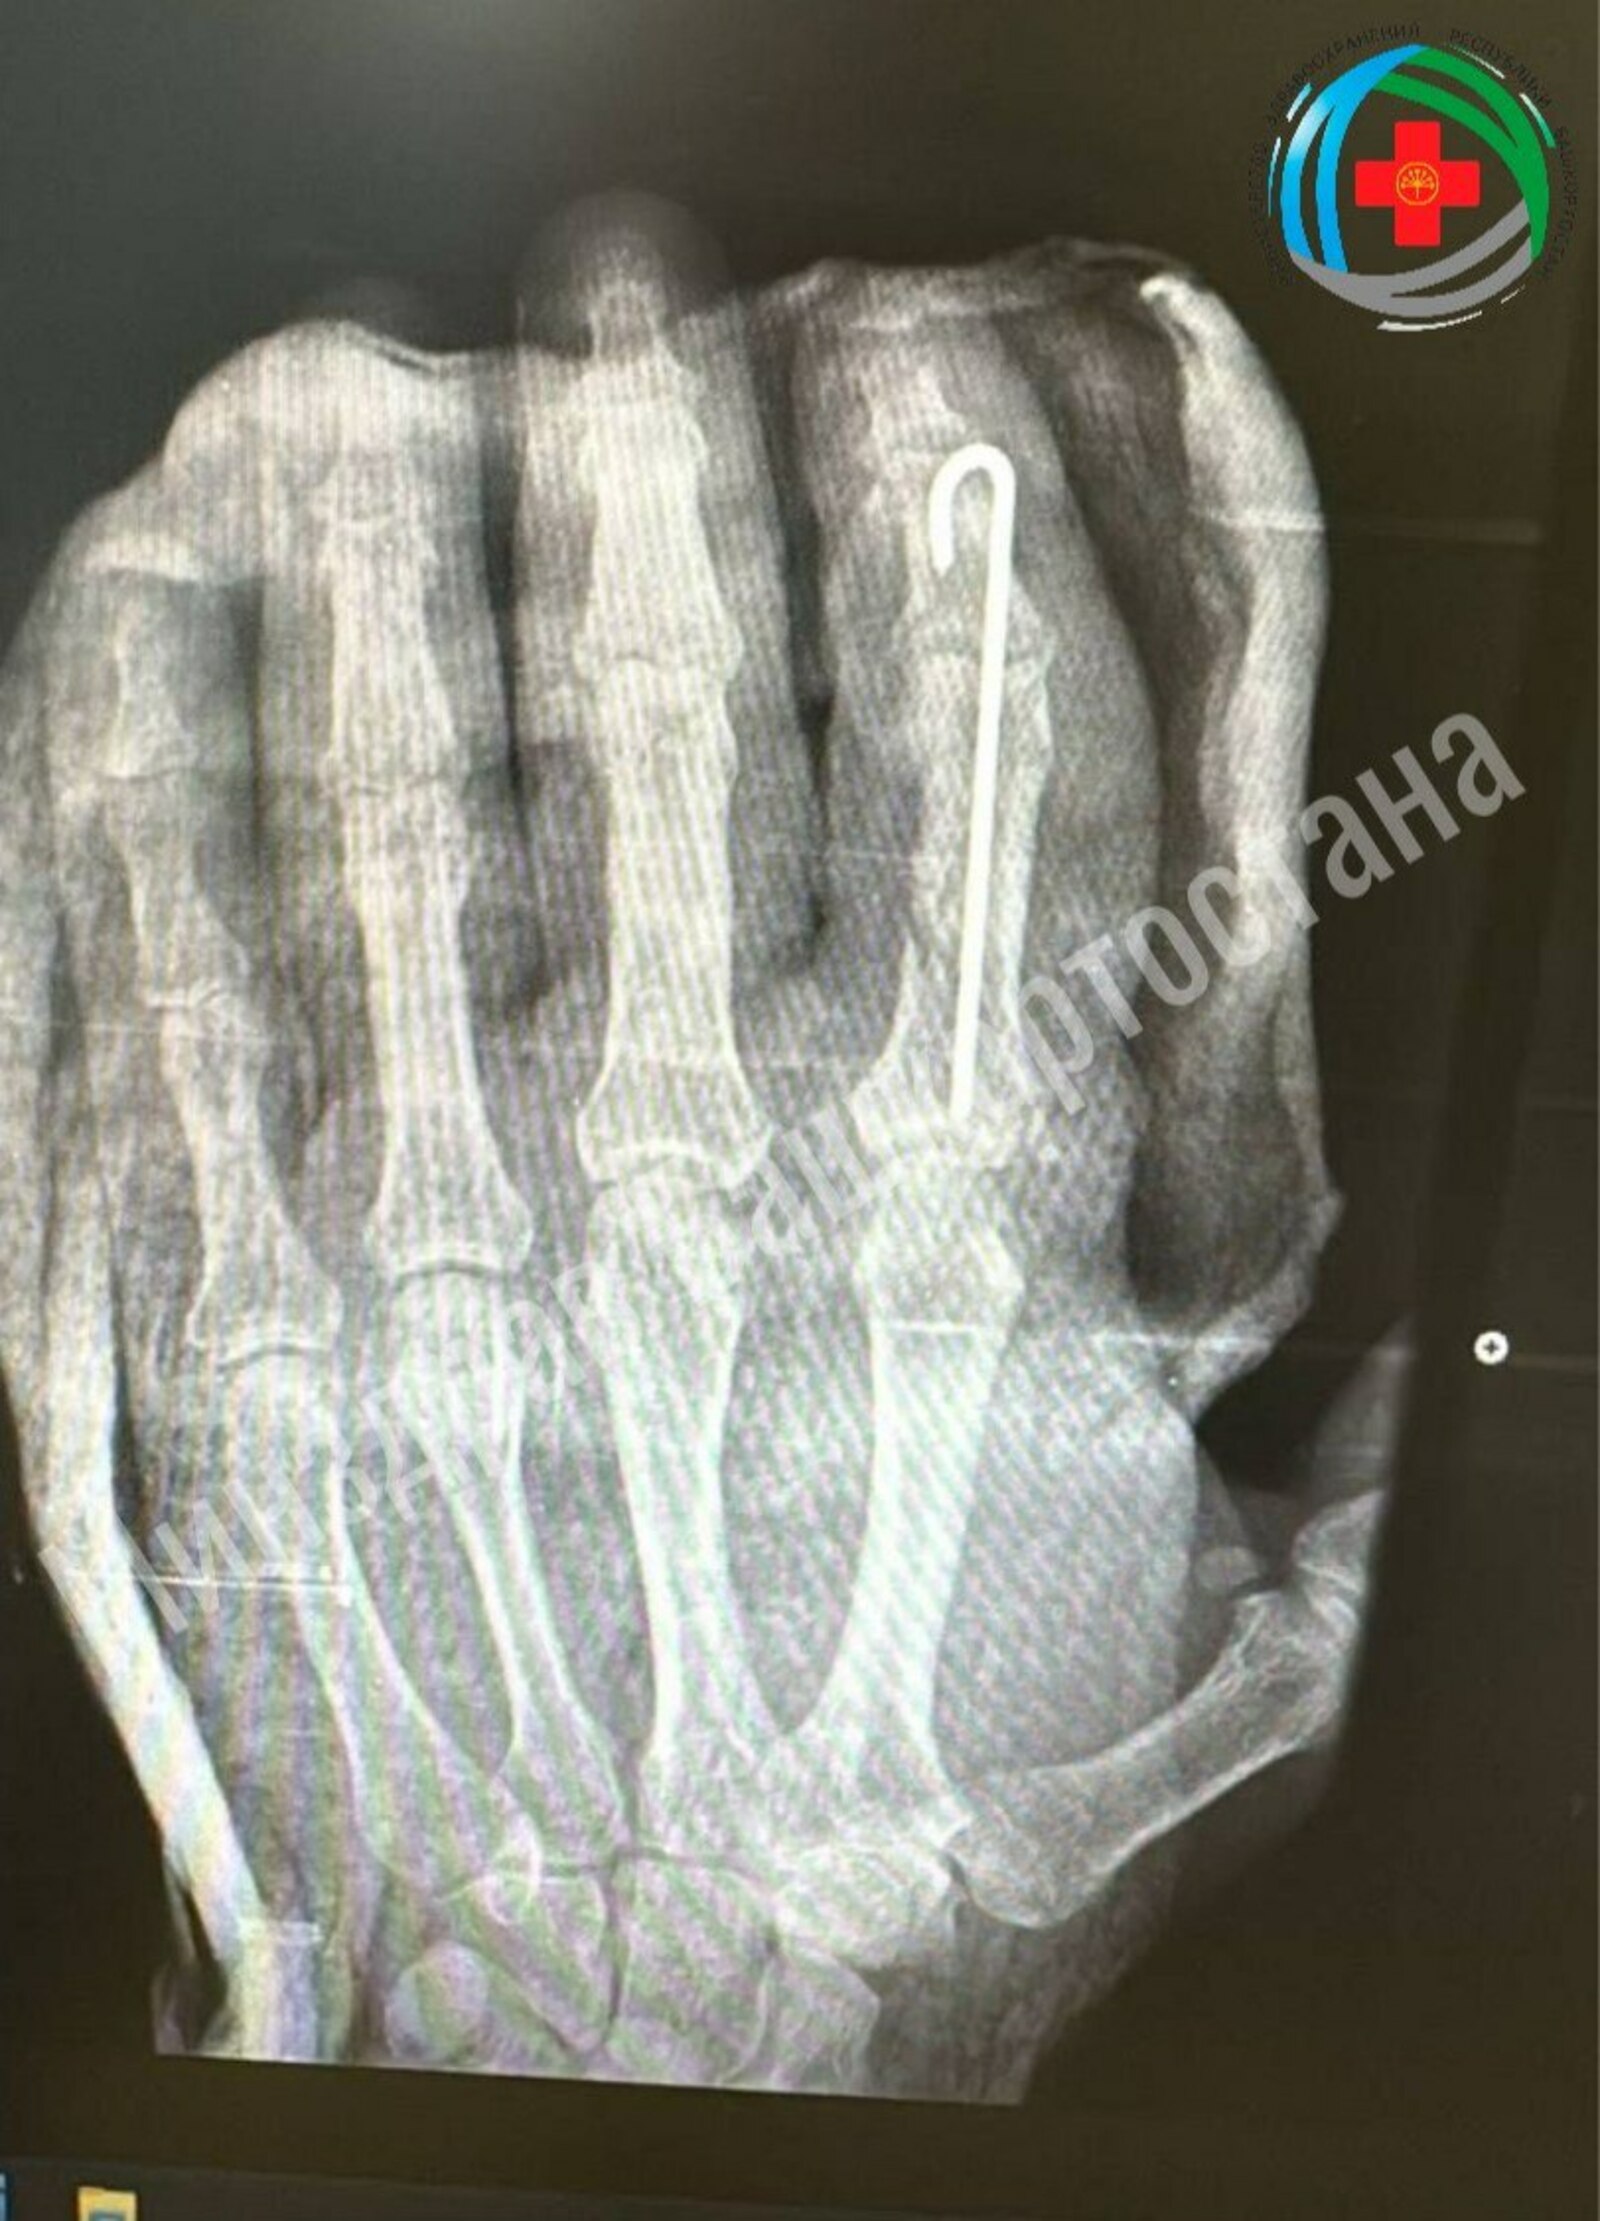

Житель Благовещенска отрубил себе палец сам, работая во дворе. Доктора провели ювелирную работу по его восстановлению, которая включала сшивание мельчайших сосудов для возобновления кровотока, точную фиксацию костей и реконструкцию мягких тканей.

Благодаря профессионализму медиков палец прижился. Сейчас пациент проходит восстановительное лечение, которое включает медикаментозную терапию, физиотерапию и лечебную физкультуру. Ожидается полное восстановление функций пальца после завершения реабилитации.

Фото: минздрав РБ.